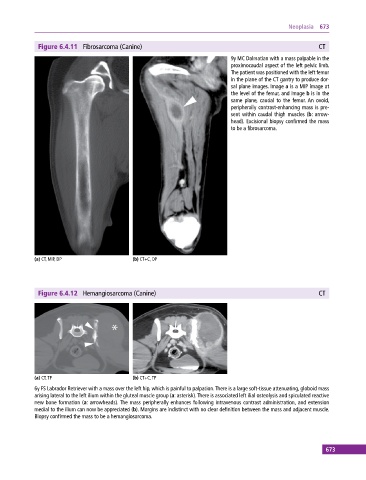

Figure 6.4.11 Fibrosarcoma (Canine) CT

9y MC Dalmatian with a mass palpable in the

proximocaudal aspect of the left pelvic limb.

The patient was positioned with the left femur

in the plane of the CT gantry to produce dor-

sal plane images. Image a is a MIP image at

the level of the femur, and image b is in the

same plane, caudal to the femur. An ovoid,

peripherally contrast‐enhancing mass is pre-

sent within caudal thigh muscles (b: arrow-

head). Excisional biopsy confirmed the mass

to be a fibrosarcoma.

(a) CT, MIP, DP (b) CT+C, DP

Figure 6.4.12 Hemangiosarcoma (Canine) CT

(a) CT, TP (b) CT+C, TP

6y FS Labrador Retriever with a mass over the left hip, which is painful to palpation. There is a large soft‐tissue attenuating, globoid mass

arising lateral to the left ilium within the gluteal muscle group (a: asterisk). There is associated left ilial osteolysis and spiculated reactive

new bone formation (a: arrowheads). The mass peripherally enhances following intravenous contrast administration, and extension

medial to the ilium can now be appreciated (b). Margins are indistinct with no clear definition between the mass and adjacent muscle.

Biopsy confirmed the mass to be a hemangiosarcoma.